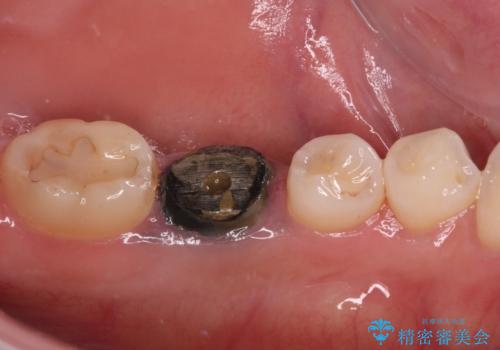

- 奥歯の銀歯が外れたことをきっかけに、全ての銀歯をセラミックに替えたいとのことで来院された患者様です。

第一大臼歯4本と、メタルインレーが装着されている2歯をセラミッククラウンならびにセラミックインレーにて補綴治療・修復治療を行うこととしました。